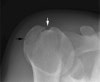

Shoulder X-ray의 Normal variation2016-10-12카테고리 51원본 보기1. Os acromiale 2. Rhomboid fossa 3. Bicipital groove ← 이전 글Acromion index다음 글 →족하수(Foot drop) : 갑자기 발목이 올라가지 않아요같은 카테고리 글2017-05-06Sulcus sign : 하방 불안정성을 조사하는 검사2017-05-05부하 전위 검사(Load and Shift Test) : 전방 불안정성을 조사하는 검사2017-05-04어깨 전방 불안정 검사(Anterior apprehension test) : 전방 불안정성을 조사하는 검사← 전체 글로 돌아가기